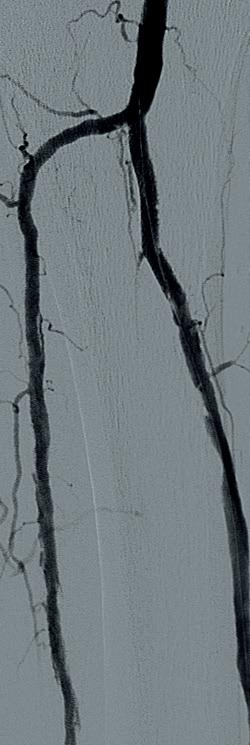

Ultrasound-guided access was obtained in the left common femoral artery and right lower extremity angiography confirmed nonobstructive inflow disease with tandem calcified 70 and 80% P1 as well as P2 extending into P3 disease. The anterior tibial

artery was noted to have a highgrade stenosis proximally with severe diffuse disease throughout its course, with essentially calcified occlusive disease distally with diffuse disease of the dorsalis pedis artery. The TP trunk was occluded proximally with complete occlusions of the TP trunk peroneal and posterior tibial vessels, with reconstitution of the posterior tibial artery above the ankle via geniculate collaterals. There was moderate diffuse disease of the plantar vessels as well (Figure 2a–c).

A 6F Ansel sheath (Cook Medical) was placed in the right CFA, and the anterior tibial occlusion was crossed with an Abbott Command 0.014” wire, followed by treatment of the popliteal lesions with a 6.0x60mm IVL catheter followed by drugcoated balloon (DCB) angioplasty with a Bard 6x150 Lutonix balloon, with reduction to a <30% residual. The right anterior tibial artery was treated with a 3.5x60mm

IVL catheter along a ~20cm segment of the lesion, followed by percutaneous transluminal angioplasty (PTA) with a 3x3.5x210mm Nanocross balloon (Medtronic), with an excellent result without recoil, despite the heavy calcific burden of disease. Antegrade traversal of the TP trunk and posterior tibial arteries was unsuccessful despite an escalating wire strategy, so

the posterior tibial artery was accessed in a retrograde manner with ultrasound guidance. The 0.014” Abbott Command wire was eventually delivered to the common femoral artery using a Quick-Cross 0.014” support catheter (Spectranetics) and exteriorised using a 7mm goose neck snare (Microvena). IVL of the TP trunk and proximal posterior (approximately 20cm of treatment length) tibial artery was performed with a 3.5x40 S4 IVL catheter in less than five minutes. This was followed by PTA distally with a tapered 3x3.5x210mm Nanocross balloon. A 4x38mm Medtronic Resolute Onyx DES was placed to treat a residual dissection in the TP trunk with final angiography demonstrating three-vessel runoff to the foot (Figure 3a–c). Remarkably, the anterior tibial IVL/PTA result showed no appreciable recoil, despite the fact that it took over 90 minutes to complete the TP trunk and posterior tibial reconstruction. He was discharged later that day. He later underwent second toe amputation and successfully healed his wounds.

Figure 3a Figure 3b Figure 3c